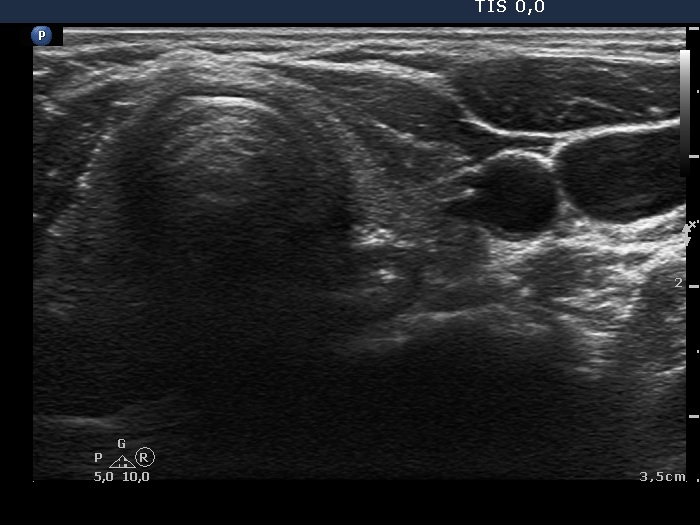

Follow-up examination 3 years later (second row of images):

Ultrasonography: The thyroid was unchanged. The lesions in the dorsal part of the right lobe increased in size and a small hypoechogenic area appeared in the ventral part of the left lobe.

Wash-out thyroglobulin and parathormone levels were determined, the former was 74.4 ng/mL while the latter was above 474 pg/mL.

A repeat blood test was performed. Serum thyroglobulin resulted in 11.9 ng/mL while serum parathormone level did in 180.7 pg/mL. Serum calcium was 2.94 mM/L, serum phosphorus 0.69 mM/L.

Scintigraphy disclosed parathyroid enlargement not only in the right but even in the left side.

Surgery was performed. Histopathology disclosed hyperplasia of all four parathyroids.